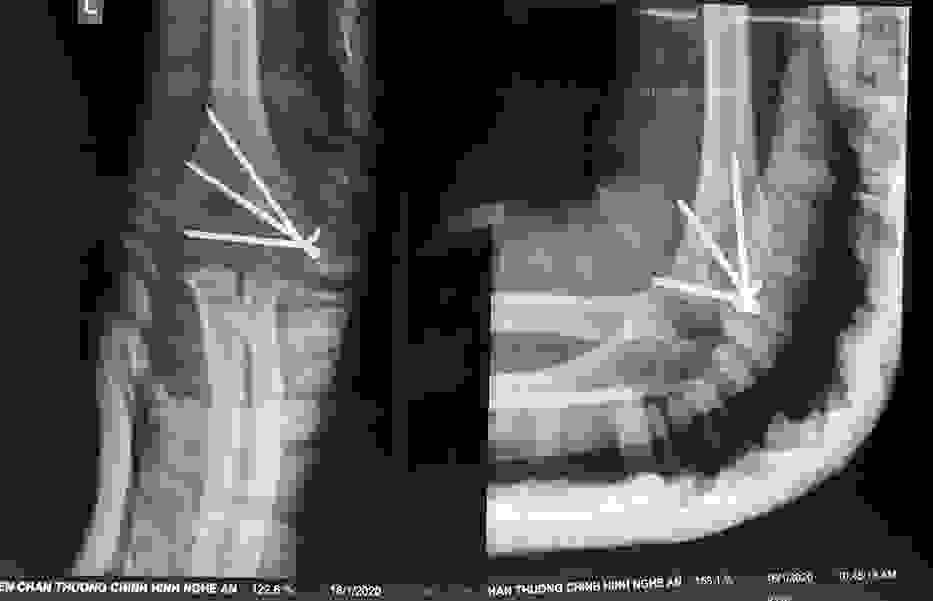

Phẫu thuật thành công ca bệnh hiếm gặp...khớp giả bẩm sinh xương chày

26/06/2019 17:00

Đã xem: 3454

Bệnh viện Chấn thương- Chỉnh hình Nghệ An, vừa phẫu thuật thành công cho bệnh nhi khớp giả bẩm sinh xương chày